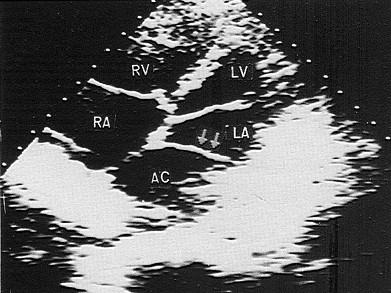

该病例最可能的诊断?(?)A.三房心B.瓣上环C.完全性肺静脉畸形引流D.冠状静脉窦扩张E.主动脉,肺动脉间隔缺损

问题 该病例最可能的诊断?(?)

选项 A.三房心 B.瓣上环 C.完全性肺静脉畸形引流 D.冠状静脉窦扩张 E.主动脉,肺动脉间隔缺损

答案 A